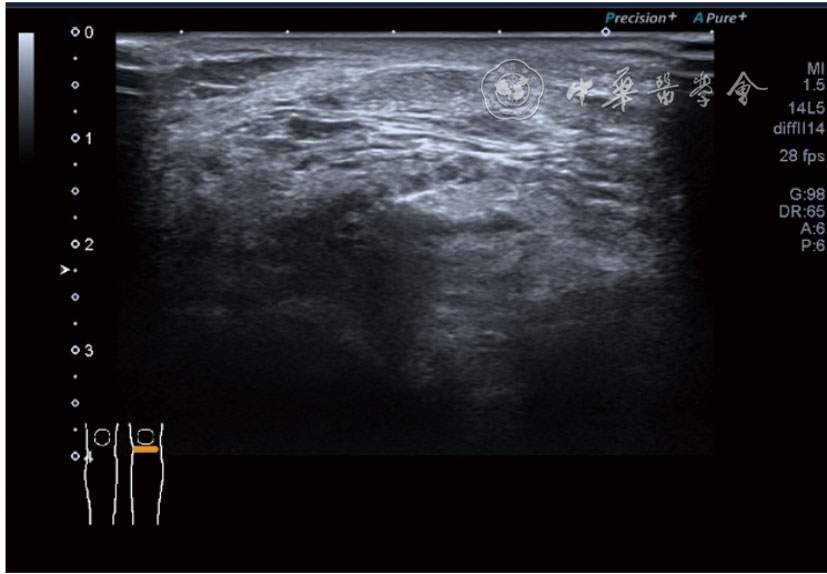

(五)超声影像学表现

患者采取侧卧位,患肢在上,屈膝20°。应用10~18 MHz高频线阵探头,扫查深度1~3 mm。长轴和短轴结合双侧对比扫查。超声影像学所见:短轴可见卡压腓总神经近端增粗,面积增大;长轴可见腓总神经卡压处变细,其近侧肿胀、回声减低,而在卡压远侧则表现正常(图35);一些受压严重者可以出现神经周围积液,卡压神经部位的筋膜增厚(图36);受压神经内血流增加对临床诊断意义更大(图37);探头在病变神经处加压常可引起神经刺激症状。腓总神经支配的肌肉有失神经支配改变,表现为肌肉回声增高和肌肉萎缩(图38)。

图38 肌肉回声增强和肌肉萎缩超声图像